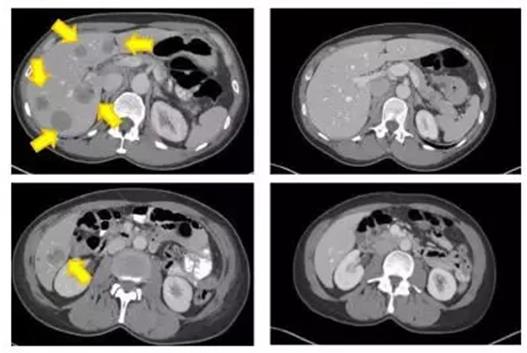

KRAS G12D突变的结直肠癌患者经过TIL治疗后,患者肺部的7个转移灶中6个病灶消失殆尽,其中三个完全消失,患者在4年后仍然没有疾病进展。